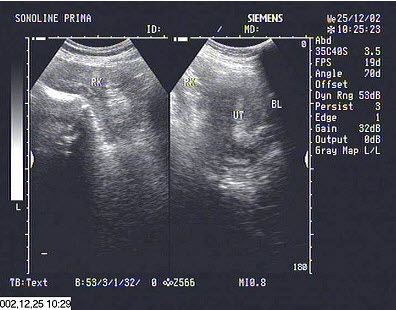

10、单项选择题

超声探查,子宫旁边有一类似肾脏的光团,最可能诊断为()